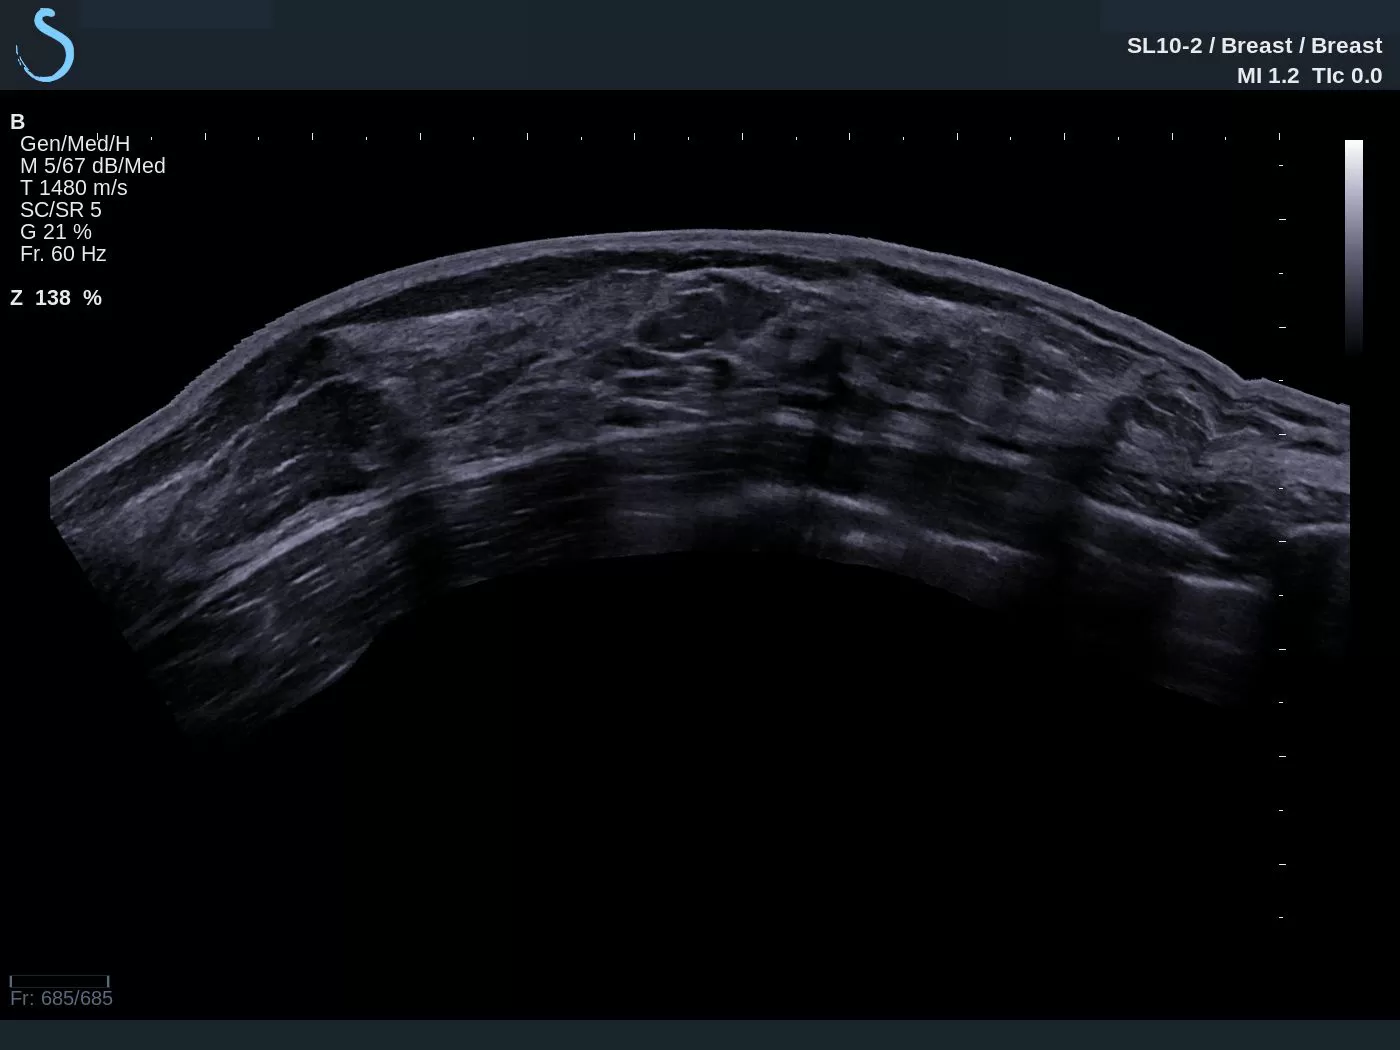

The Aixplorer Ultimate ultrasound unique capabilities of Shearwave Elastography, are going to be presented in the workshop which will be held on 29/9/2018, during the ultrasound – elastography workshop.

Find out how SWE can help you increase the sensitivity of the ultrasound exam, the biopsy predictive value, and how a DCIS can be upgraded to IDC.